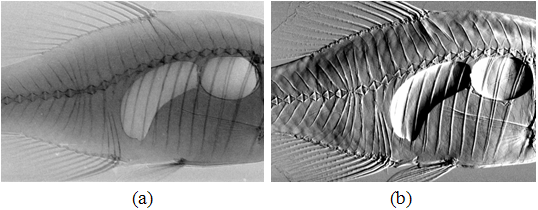

图8. 大鼠肝血管的衍射增强成像[16]。图(a)和(d)是在摇摆曲线的两个趾位拍摄的图像,(b)和(e)是在摇摆曲线的两个半腰位置拍摄的图像,(c)是在摇摆曲线的峰位拍摄的图像,(f)是计算的折射像。